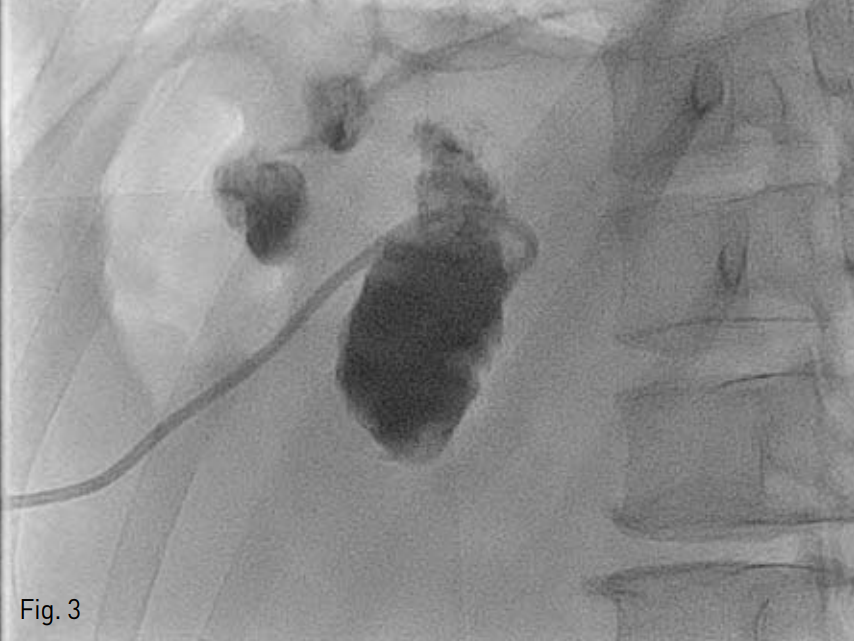

리도카인으로 국소마취를 시행한 후 초음파 유도 하에 비장문에 위치한 농양을 비장을 겅유하이 18G Chiba needle로 천자하였다(Fig. 2). 0.035-inch 유도철사(Terumo, Tokyo, Japan)을 삽입한 뒤 이를 따라 8.5-Fr pigtail catheter(Cook, Bloomington, IN, USA)를 삽입하여(Fig. 3) 40cc의 고름을 배액 하였다.

Fig. 2

Gray scale ultrasound image shows linear hyperechoic Chiba needle inserted through the spleen.